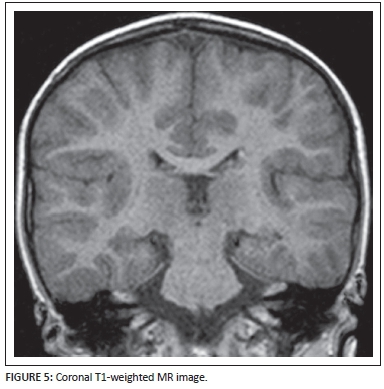

A three and a half year-old male child was referred for neuroimaging under general anaesthesia for intractable seizures. These are selected MR images.

Describe the relevant imaging findings and formulate the most appropriate clinical diagnosis. Please submit your response to misser@lakesmit.co.za not later than 30 November 2015. The winning respondent will receive a R1000 award from the RSSA. A detailed diagnosis and discussion will be presented in the next issue of the SAJR.